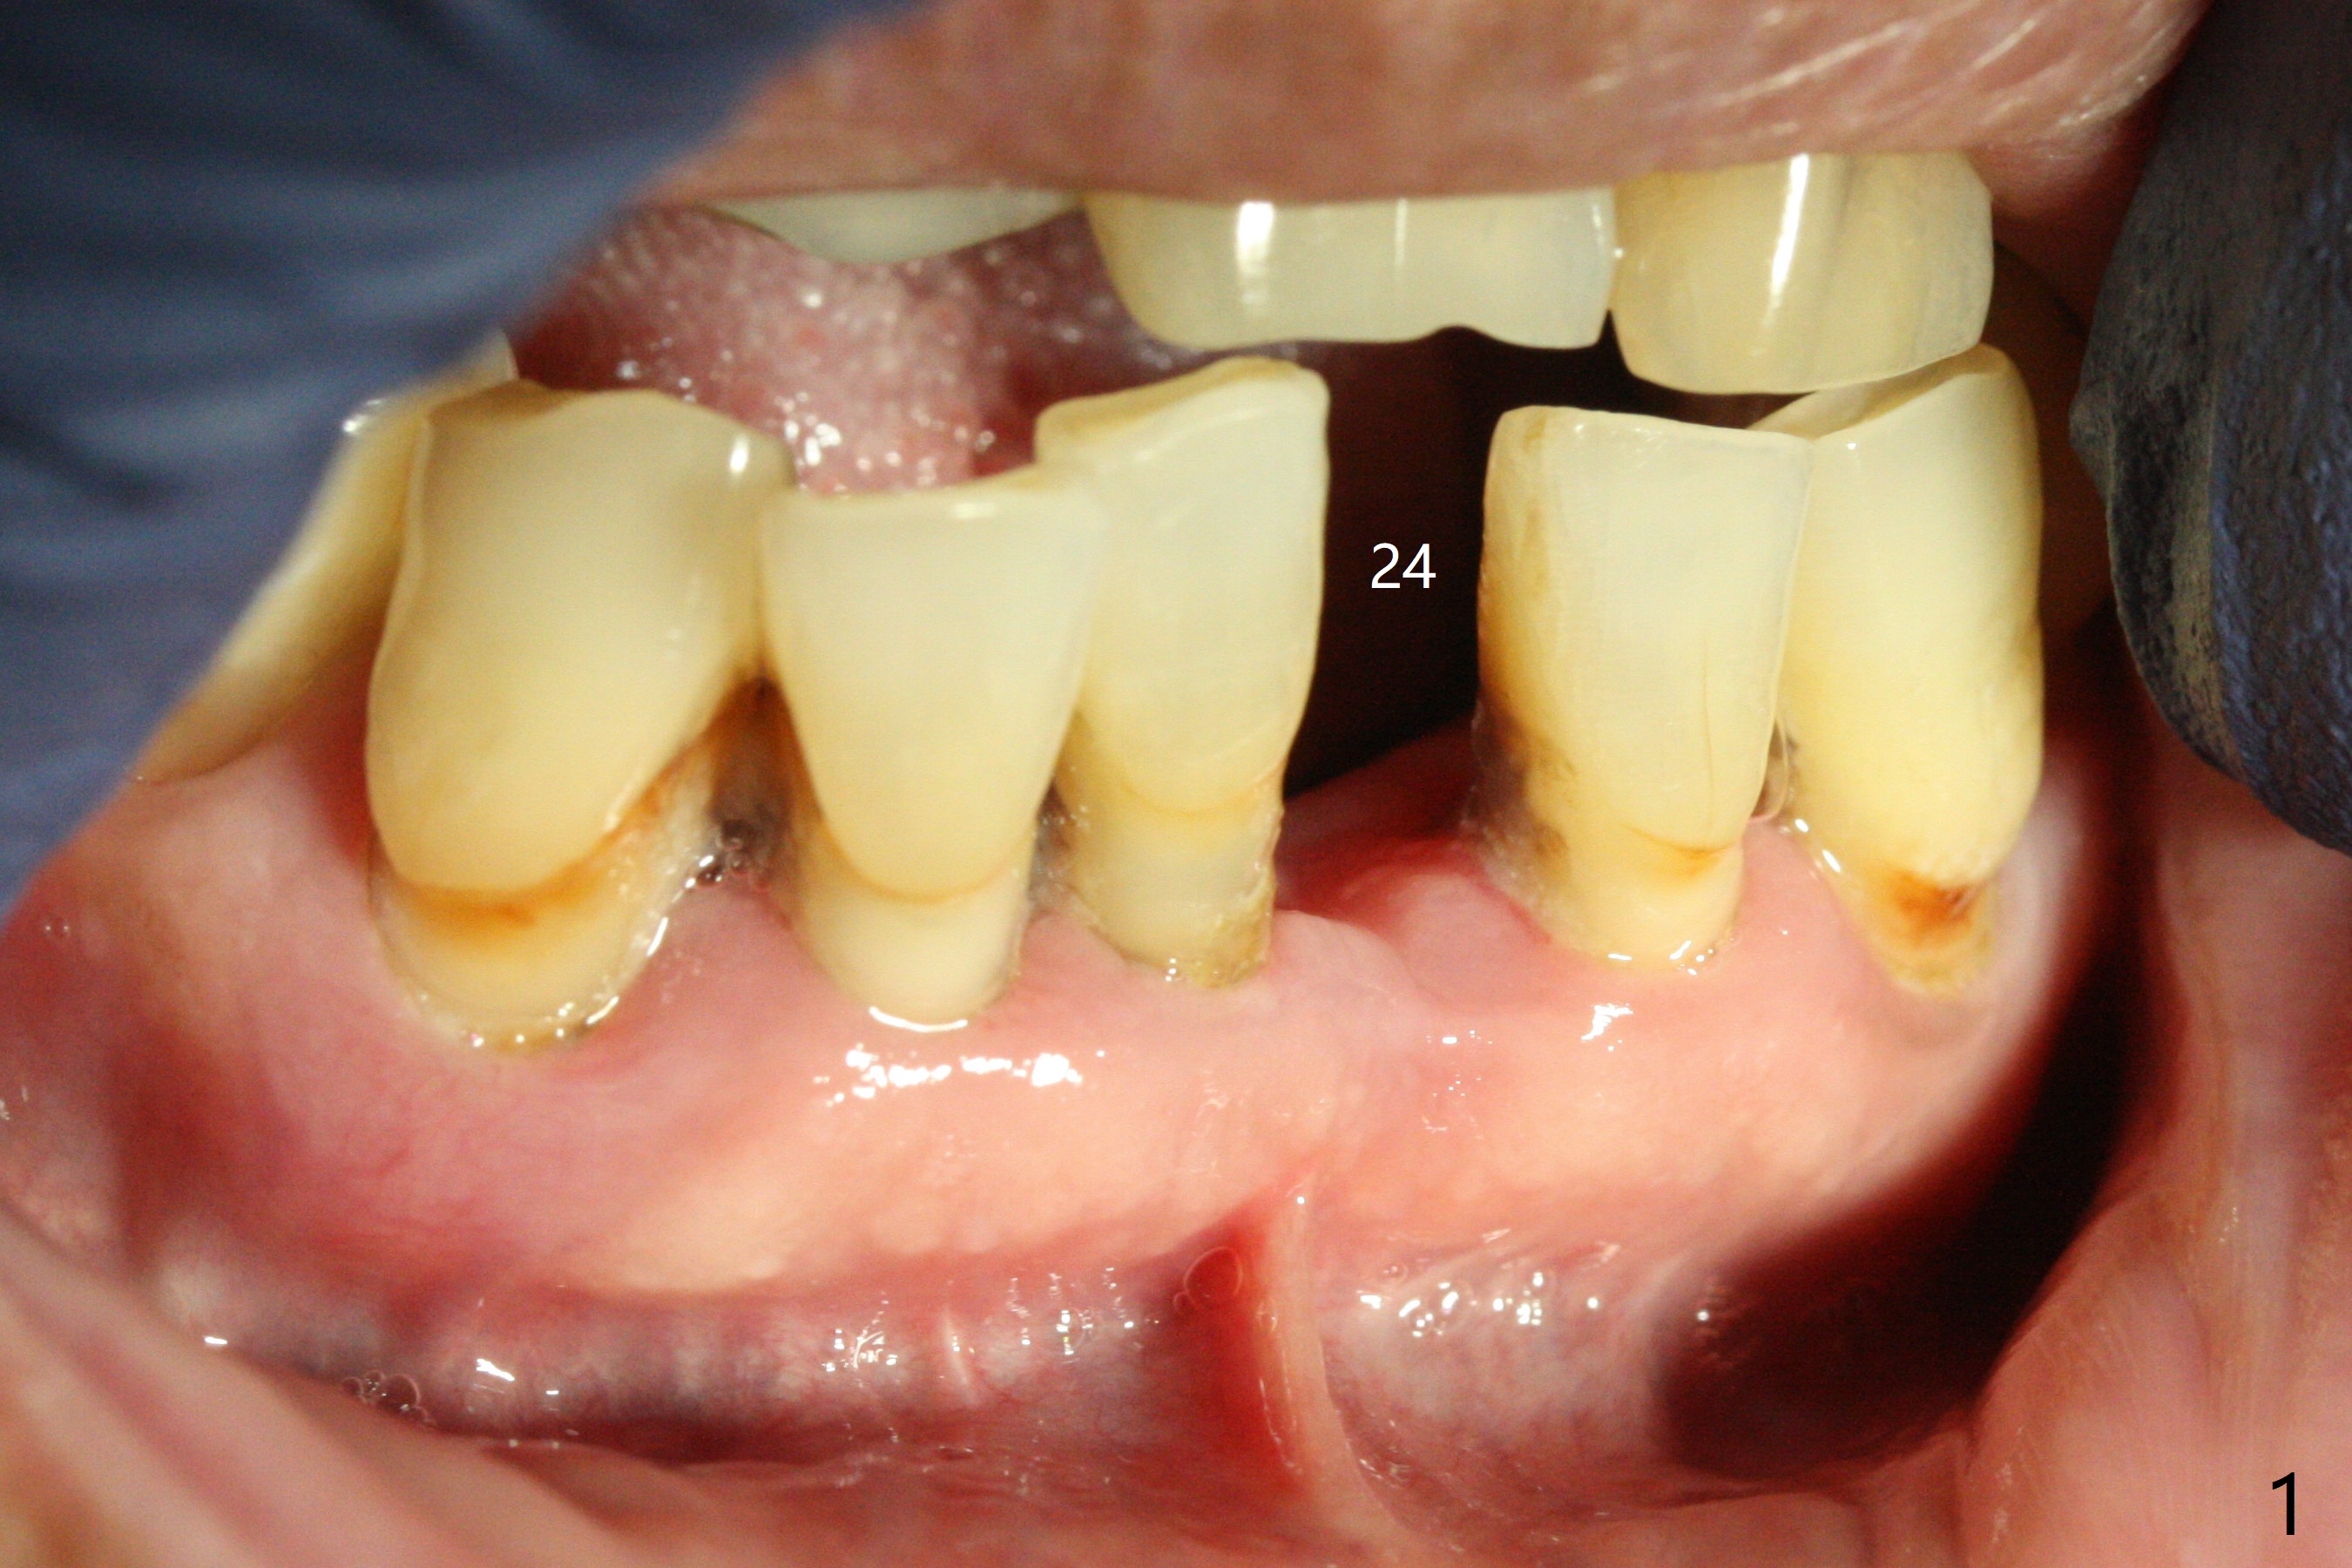

When the patient returns, the tooth #24 has exfoliated, while the ones at #25 and 26 has mobility III (Fig.1). The patient requests the tooth #23 extraction (Fig.2), but not #27. After SRP and extraction, osteotomy is initiated mesial to the sockets #23,25 and 26 (Fig.3,4) with intention to place 3 1-piece implants for 3 incisor crowns (Fig.5,6). Following Vanilla graft (Fig.5 *) a splinted provisional is fabricated to close the sockets (Fig.6). Peri-implant spaces close 5.5 months postop (Fig.7). Impression is taken after reprep for margin and parallelism (Fig.8). The final restoration consists of #23 single unit crown and #24-26 3-unit FPD (Fig.9). It appears that 2.5 mm 1-piece implants are not too small for the lower incisors (Fig.10-12), especially the central one (Fig.11). There may be perforation in the apical half of the lingual plate (L in Fig.10). The patient is not pleased with the shade of the #24-26 3-unit FPD (Fig.13 (6 months post cementation)). There is metal show through the abutments (*).